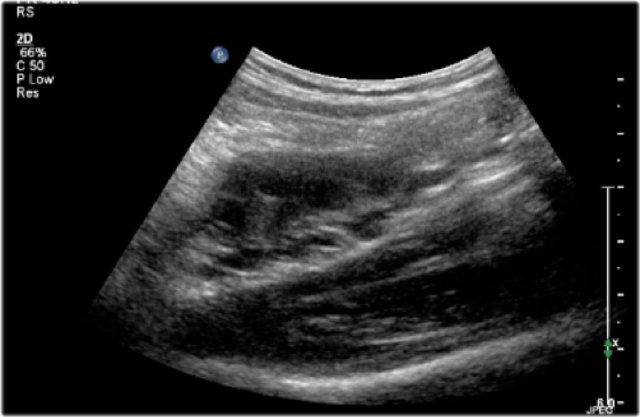

Một bé trai 1 tuổi được chuyển đến với chẩn đoán u nguyên bào thận dạng nang.

Siêu âm phát hiện một nang lớn ở trung tâm ổ bụng.

Khi khảo sát từ hông trái bằng đầu dò tuyến tính tần số cao, có thể thấy một ít mô nhu mô bao quanh các đài thận giãn rất to. Hình ảnh này phù hợp với ứ nước thận mức độ nặng.

Ban đầu, người ta cho rằng có một số thành phần đặc trong nang.

Tuy nhiên, khi ấn đầu dò, các thành phần này được xác định là cặn lắng.

MRI cho thấy hình ảnh tổng quan hơn về tình trạng ứ nước thận.

Nguyên nhân là do hẹp khúc nối bể thận – niệu quản.

Thận trái có chức năng phân chia 33% trên xạ hình thận.

Phẫu thuật tạo hình bể thận đã được thực hiện thành công.